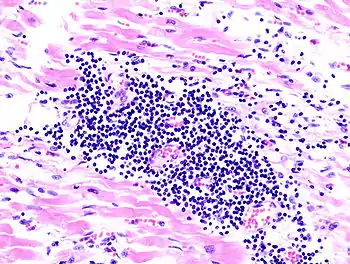

| A microscope image of myocarditis at autopsy in a person with acute onset of heart failure | |

The gold standard is the biopsy of the myocardium, in general done in the setting of angiography. A small tissue sample of the endocardium and myocardium is taken and investigated. The cause of the myocarditis can be only identified by a biopsy. Endomyocardial biopsy samples are assessed for histopathology (how the tissue looks like under the microscope): myocardial interstitium may show abundant edema and inflammatory infiltrate, rich in lymphocytes and macrophages. Focal destruction of myocytes explains the myocardial pump failure.[10] In addition samples may be assessed with immunohistochemistry to determine which types of immune cells are involved in the reaction and how they are distributed. Furthermore, PCR and/or RT-PCR may be performed to identify particular viruses. Finally, further diagnostic methods like microRNA assays and gene-expression profile may be performed.